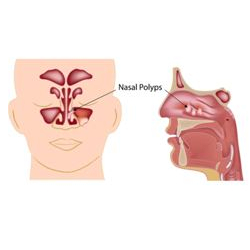

FESS for Nasal polyposis

The standard procedure to remove nasal polyps is Functional Endoscopic Sinus Surgery (FESS). The surgeon will insert a small tube with a tiny camera into the nostrils and guide it into the sinus cavities and the polyps will be removed, for this procedure Dr.Yashaswi is an expert in FESS surgery in Bangalore